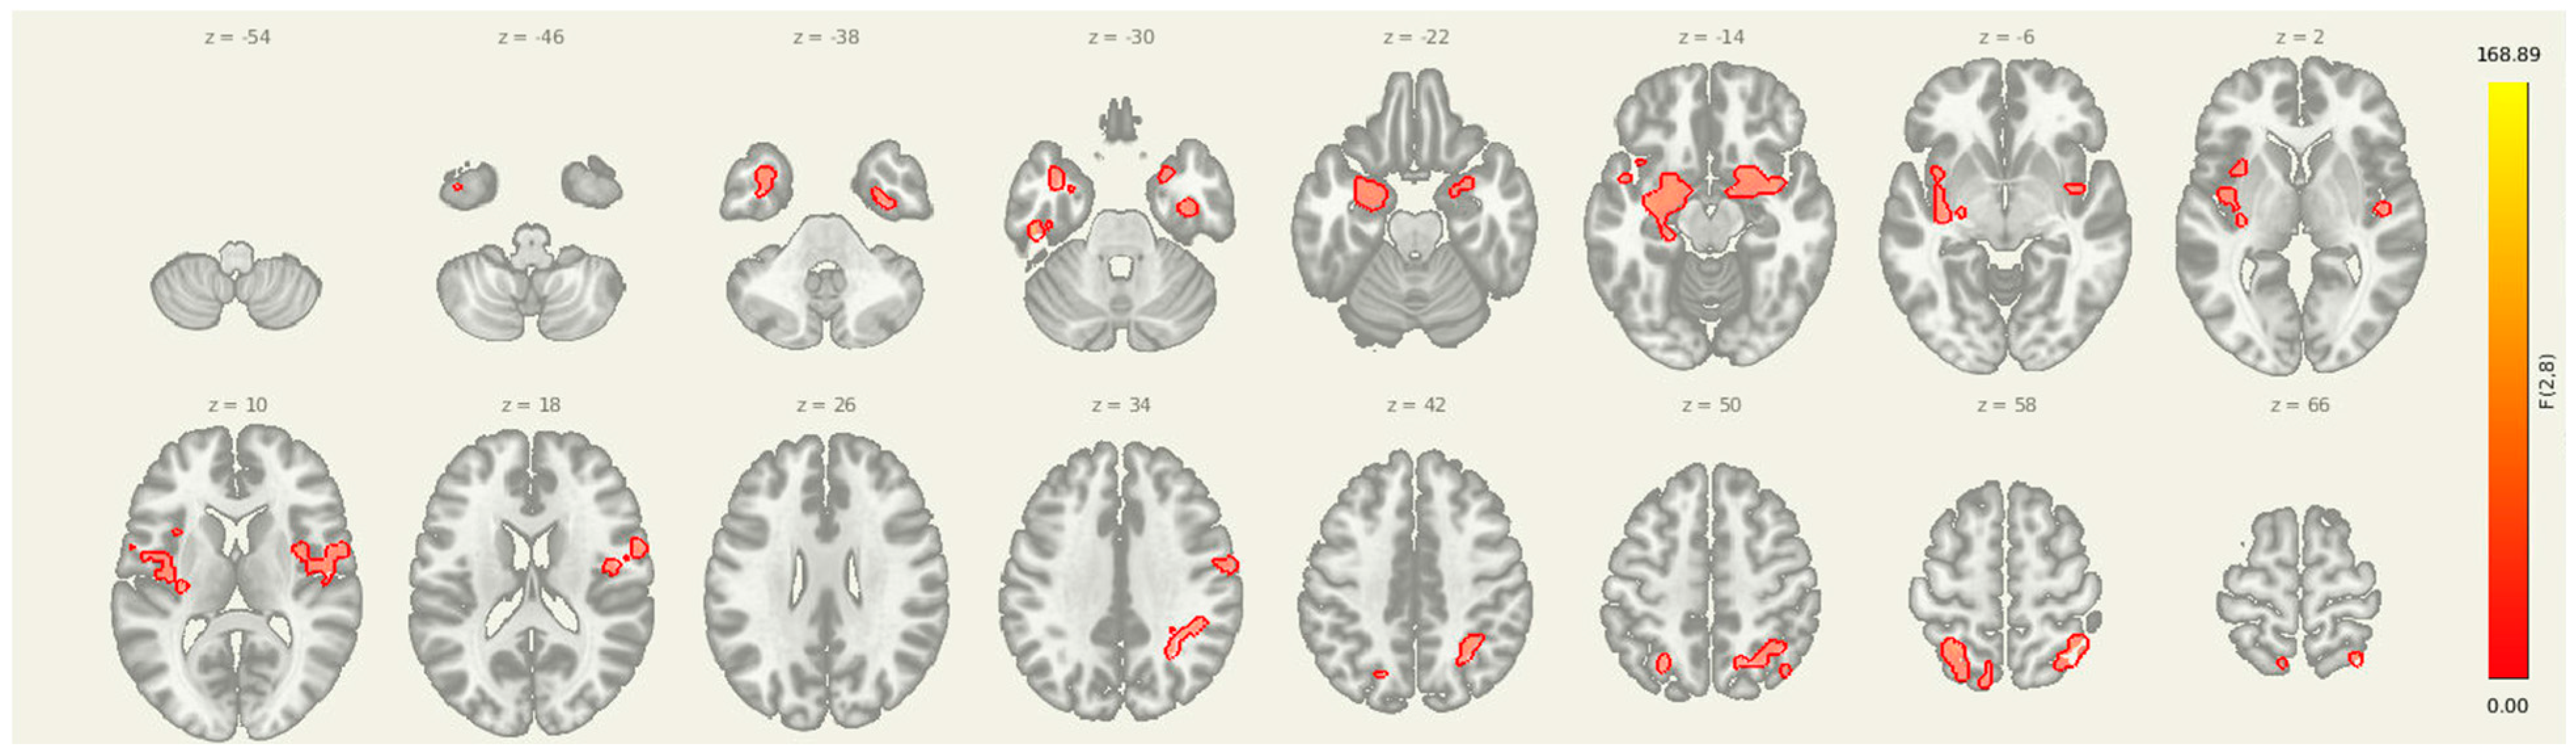

Figure 2.

Multi-slice view of amygdala seed connectivity at pre-intervention. Displayed clusters correspond to those reported in Table 2, showing significant resting-state connectivity between the amygdala and bilateral cortical regions, including sensorimotor and prefrontal cortices. All results are thresholded at p-FDR < 0.05 and shown in MNI space.

3.2. Pre Amygdala Seed

Prior to intervention, seed-to-voxel analysis from the amygdala revealed widespread connectivity with multiple cortical and subcortical regions (Figure 1). Significant clusters were observed in bilateral sensorimotor and frontal areas, including the left parahippocampal gyrus (MNI: −36, +06, −28; cluster size = 1396 voxels; p-FDR < 0.001), right superior parietal lobule (+38, −56, +60; 575 voxels; p-FDR < 0.001), right insular cortex (+46, −06, +16; 406 voxels; p-FDR < 0.001), and right thalamus (+18, +10, −16; 383 voxels; p-FDR < 0.001). Additional clusters were detected in the left superior parietal lobule, right cerebellum, and prefrontal cortex, further supporting elevated amygdala connectivity within regions implicated in sensory integration, emotional processing, and motor readiness (Figure 2).